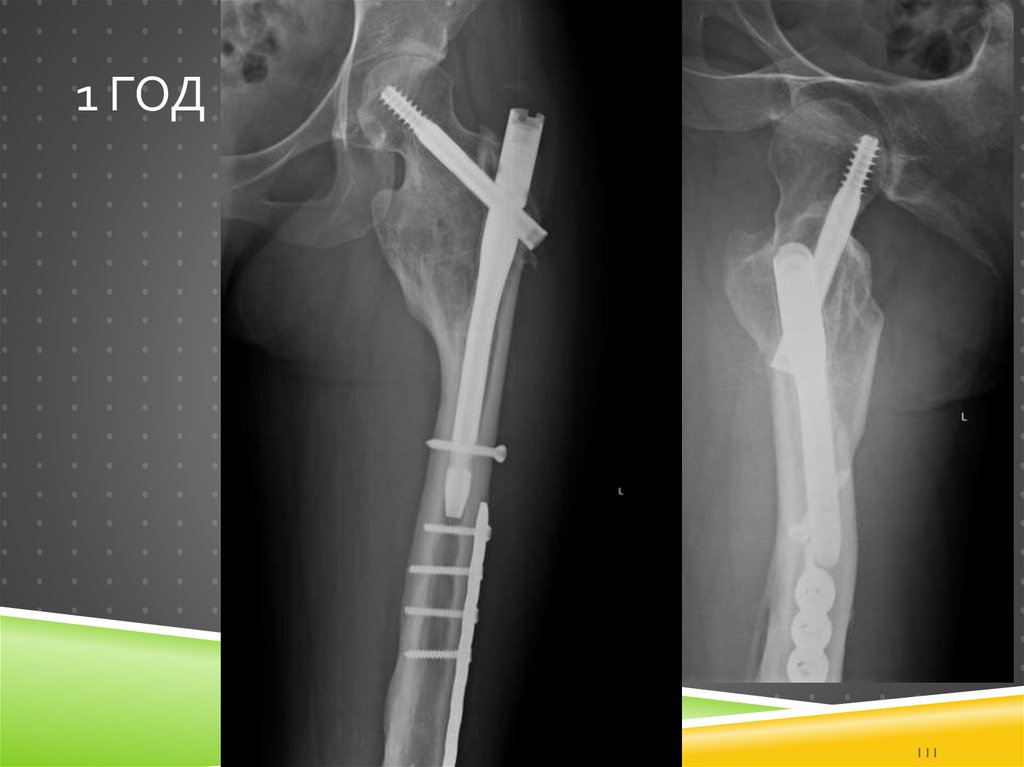

111. 1 год

1 ГОД

111